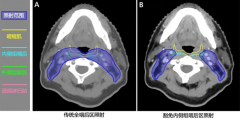

The BMJ | 鼻咽癌“内侧组咽后区豁免放疗”改善咽期吞咽功能:多中心随机3期研究的5年随访结果

主要发现 The BMJ 近日发表的一项随机3期临床研究,公布了鼻咽癌内侧组咽后区豁免放疗减毒新技术的最终生存分析及探索性结果。该研究不仅证实了这一技术的长期吞咽功能获益,再次......【详情】

2026-04-08